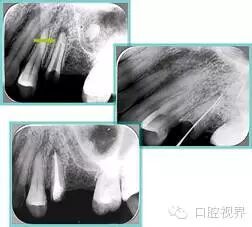

7. 器械折断

右图及下图为器械折断的 X 线片。箭头处示折断器械。

口腔H锉怎么消毒根管治疗的细节把握(细节决定成败)_https://www.jmylbn.com_新闻资讯_第27张 口腔H锉怎么消毒根管治疗的细节把握(细节决定成败)_https://www.jmylbn.com_新闻资讯_第28张

解决方法:( 1 )取出。( 2 )通过。( 3 )重新确定工作长度,充填。( 4 )根尖手术。

器械折断可以不用取出,取出的原因多是患者心理因素。留在里面的器械关键是进行消毒,预防性使用抗感染药物,预防感染。